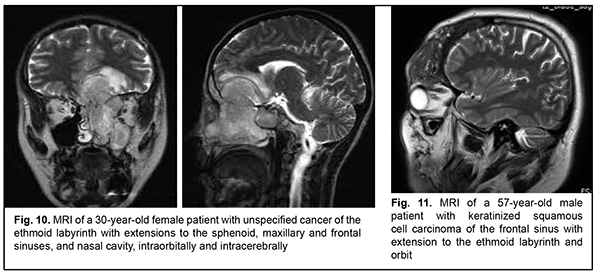

Schwannoma develops from Schwann cells of nerves. Among our patients with schwannoma, the tumor was commonly located within the lateral skull base and extended intracranially through the natural foramina of the skull base. The degree of intracranial extension varied from mild to severe (Fig. 9). Malignant ASBOT An unspecified malignant neoplasm is associated with an extensive invasive growth with significant intracranial and intracerebral extensions, and is accompanied by cerebral swelling and cortical tumor growth. This invasive growth extends also to the orbital tissue, where the tumor grows into the periorbit and orbital fat (Fig. 10).

Keratinized squamous cell carcinoma and non-keratinized squamous cell carcinoma are similar in their course and grow locally. Their intracranial growth is mild (Figs 11, 12). Adenoid cystic carcinoma is a highly differentiated cancer that commonly grows locally at the site of origin. The tumors grow expansively (Fig. 13), and may extend intracranially and intracerebrally. Adenocarcinomas are malignant tumors of the lacrimal and salivary glands and paranasal sinuses characterized by early intracerebral invasion with an aggressive course. Fig. 14 shows the adenocarcinoma of the ethmoid labyrinth with significant intracerebral growth and perifocal edema, involvement of the falx, and extension along the anterior falx to skull base and orbit bones with invasion and destruction of these bones.